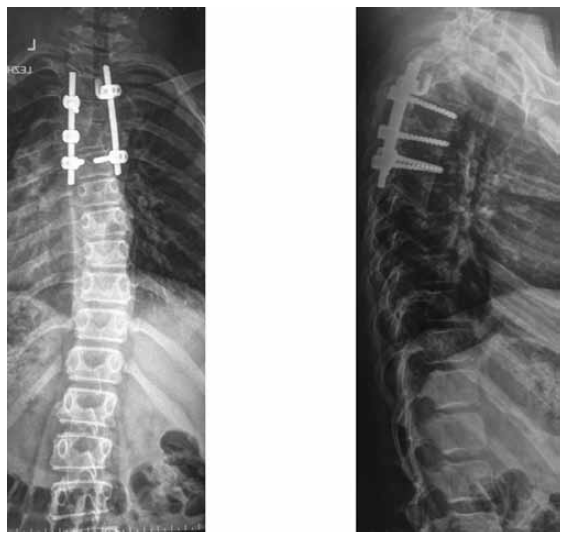

After the surgical treatment, control radiographs revealed a radical corrected local congenital spinal deformity in upper thoracic region, the multi-support surgical hardware (4 transpedicular support elements and 1 infra-laminar support hook) installed in the vertebrae Th3, Th5, and Th6 were correct and stable. Right-sided scoliotic arch at the level of the vertebrae Th7–Th10 was 15°, and the left-sided arch at the level of L1–L4 was 11° (Fig. 2).

Fig. 2. Radiographs of the spine of the patient F., 11 years old, in two views after the surgical treatment

After the surgical treatment, a completely corrected congenital local arch of curvature at the level of the posterolateral hemivertebra and reduced scoliotic deformity arches in the thoracic and lumbar regions were recorded. The size of the thoracic kyphosis was 38°, whereas that of lumbar lordosis was 42°, according to Cobb, and it was within the physiological norm. Besides, the laminar hook was installed on the concave side of the curvature at the level of the posterolateral hemivertebra due to the small size of the base of the arch of the vertebra Th3 and Th2, which did not allow the transpedicular screw to be inserted.